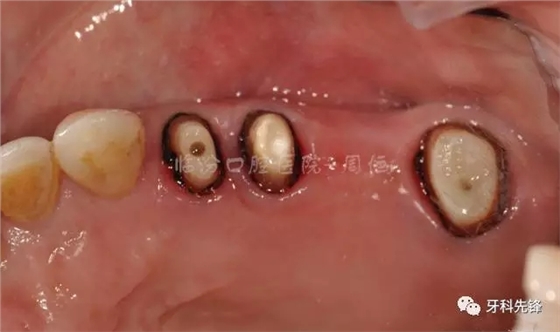

圖4拆除原修復(fù)體牙列照

檢查:15 16 17 烤瓷冠修復(fù)體,崩瓷,邊緣不密合,食物嵌塞,齦下牙石II°,冷熱診無(wú)不適,叩診(+),牙齦輕微紅腫。

14 殘冠,位于齦下2mm,牙齦顏色正常,叩診(-)